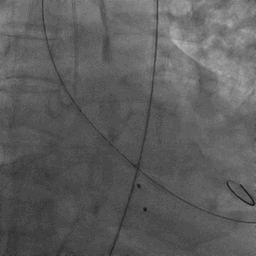

手术过程

患者麻醉方式为全麻,建立静脉通路后,穿刺右侧股静脉,预埋ProGlide缝合器,食道超声指导下房间隔穿刺成功,将Superstiff导丝送至左房,应用18F鞘管扩张穿刺部位,沿导丝将导引导管送入左房,MitraClip调整后顺利到达二尖瓣目标位置,在X线及食道超声辅助下,将Mitraclip NTR成形夹精确定位后,成功夹合二尖瓣A2-P2区,超声显示反流明显减少,多切面证实夹合组织充分,肺静脉多普勒波形由反向恢复正常,手术顺利结束,安返普通病房。

确定房间隔穿刺点:靠后

2D视图下测量大鞘长度2cm